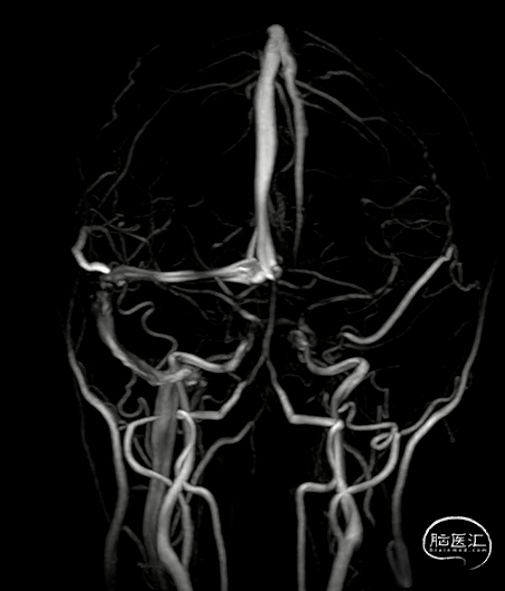

MRV

含钆的 MR 静脉造影很好地隔离了鼻窦和皮质静脉,上述几个片子,相信你可以很准确的判断出缺失的静脉窦了,那么MRV也会存在CTV相同的问题,也容易受到解剖变异的影响,真正赋予 MRV卓越灵敏度和特异性的是同步脑部 MRI。随着血栓老化,T1 和 T2 信号发生变化。

CTV与MRV:直窦和深部引流静脉消失

复查影像:深层引流系统已完全重新通畅。这并不奇怪。 据报道,近 85% 的再通发生在治疗的前 3 个月。丘脑水肿消退,但梯度回波显示残余丘脑出血。